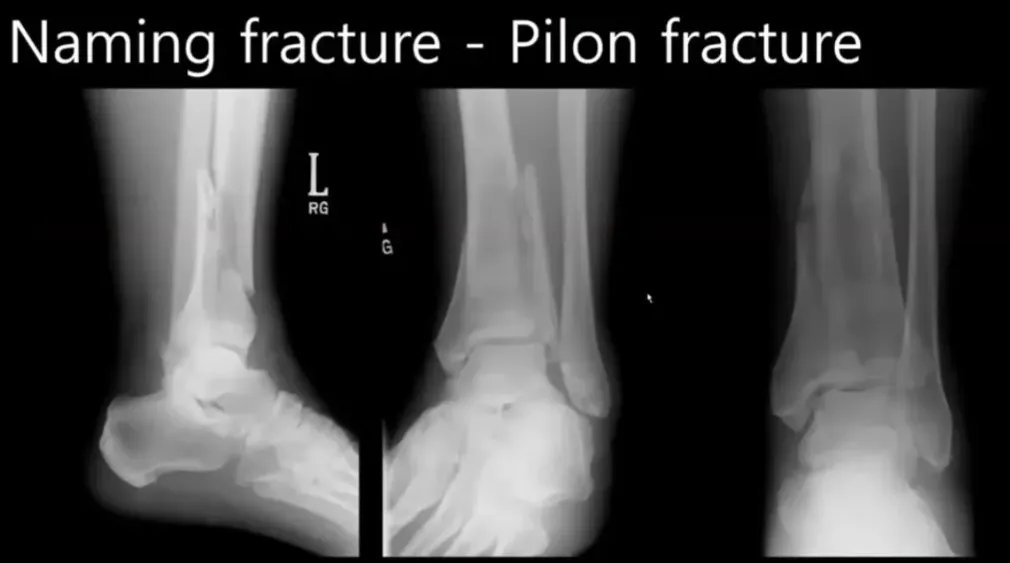

E. 필론 프랙처와 골절의 이해

필론 프랙처는 디스탈 tibia가 심각하게 부러진 상태로, 주로 발바닥 쪽에서 엑시얼 포스에 의해 발생한다 244.

드라이버 TA 사고 시, 브레이크를 밟으면서 발생하는 XCR 포스로 인해 뒤쪽에서 오블리크한 형태로 프랙처가 생긴다 246.